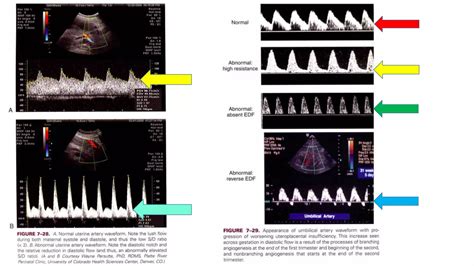

The results of a Doppler scan are expressed as waveforms. A doctor will look at the shape and regularity of these waves to assess the placental resistance. If the blood flow is smooth and consistent, it indicates a healthy exchange of oxygen and nutrients. If the waveforms suggest increased resistance, it indicates that the heart has to work harder to pump blood through the placenta, which is a significant indicator of potential fetal distress.

Understanding the Results